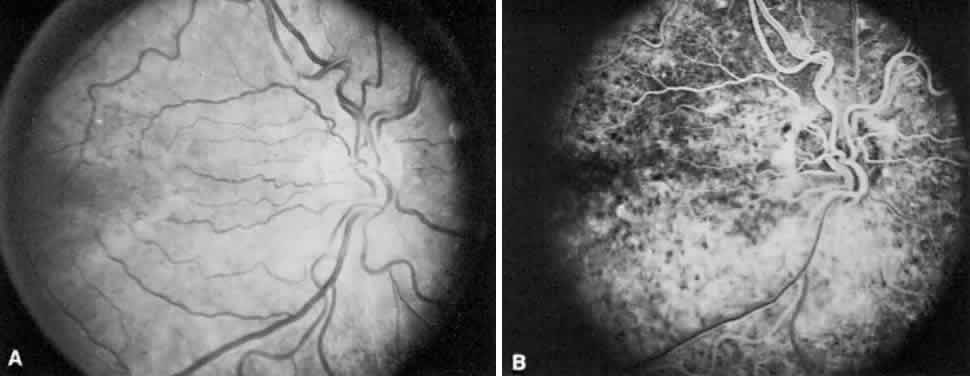

Retinopathy is the most common ocular manifestation of congenital rubella, followed in frequency by strabismus and cataract.193 It is characterized by a diffuse pigmentary disturbance (salt-and-pepper retinopathy), often more prominent on fluorescein angiography than ophthalmoscopically (Fig. 24). Usually, it is bilateral, but this is not always so.193,194 The visual acuity in eyes with retinopathy unaccompanied by cataracts or glaucoma usually is 20/20 to 20/60 (6/6 to 6/18), with a median of about 20/25 (6/7.5). Although it was formerly believed that the retinopathy was not progressive and affected the vision only mildly, several cases have been described in which a subretinal neovascular membrane developed and decreased the acuity to the 20/200 to 20/400 (6/60 to 6/120) range.195–199 In addition, affected eyes should be carefully examined for the signs of late-onset glaucoma.200 Importantly, the electroretinogram usually is normal with this disease.201

Fig. 24. A. Right fundus of a 23-year-old patient with deafness and a history of maternal infection with rubella in utero. Subtle pigmentary changes are evident, more so in the foveal area. Visual acuity in the eye was 20/25 (6/7.5). B. Fluorescein angiogram of A reveals diffuse mottled hyperfluorescence secondary to the widespread retinal pigment epithelium disturbance.